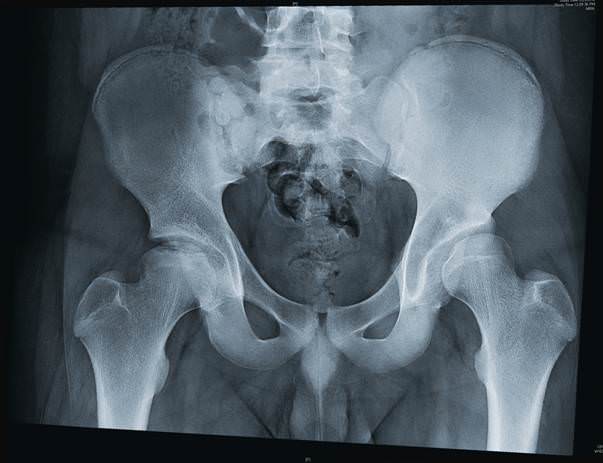

Процедура проводится в специальном кабинете. Пациент должен оголить обследуемую часть тела и пройти в рентгеновский аппарат. Далее пациенту нужно лечь на рентгеновский аппарат на спину, выпрямив конечности. В случае проверки сгибательно-разгибательных функций тазобедренного сустава рентген делается в положении сидя.

Зачастую рентген тазобедренных суставов проводится в двух проекциях:

- Снимок с прямыми ногами и с согнутыми в коленях.

- Конечностями, разведенными немного в сторону.

Во время проведения процедуры нужно не двигаться, чтобы снимок получился наиболее четким. Обычно делается несколько дополнительных снимков для более точной диагностики.

Процедура длится около 5-10 минут и является совершенно безболезненной. Чтобы не облучать другие части тела, кроме положенной, может накладываться специальный фартук из свинца.